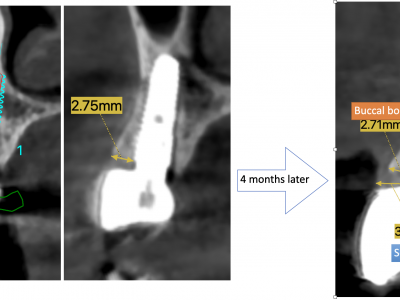

Each case is documented with clinical pictures before, after and during operation. For most of the cases there is surgical video. CBCT before, in the OP day and 4 months after, or longer period of time will demonstrate the volume of buccal bone and soft tissue. Depends of time available, between 13 and 20 clinical cases can be shown.